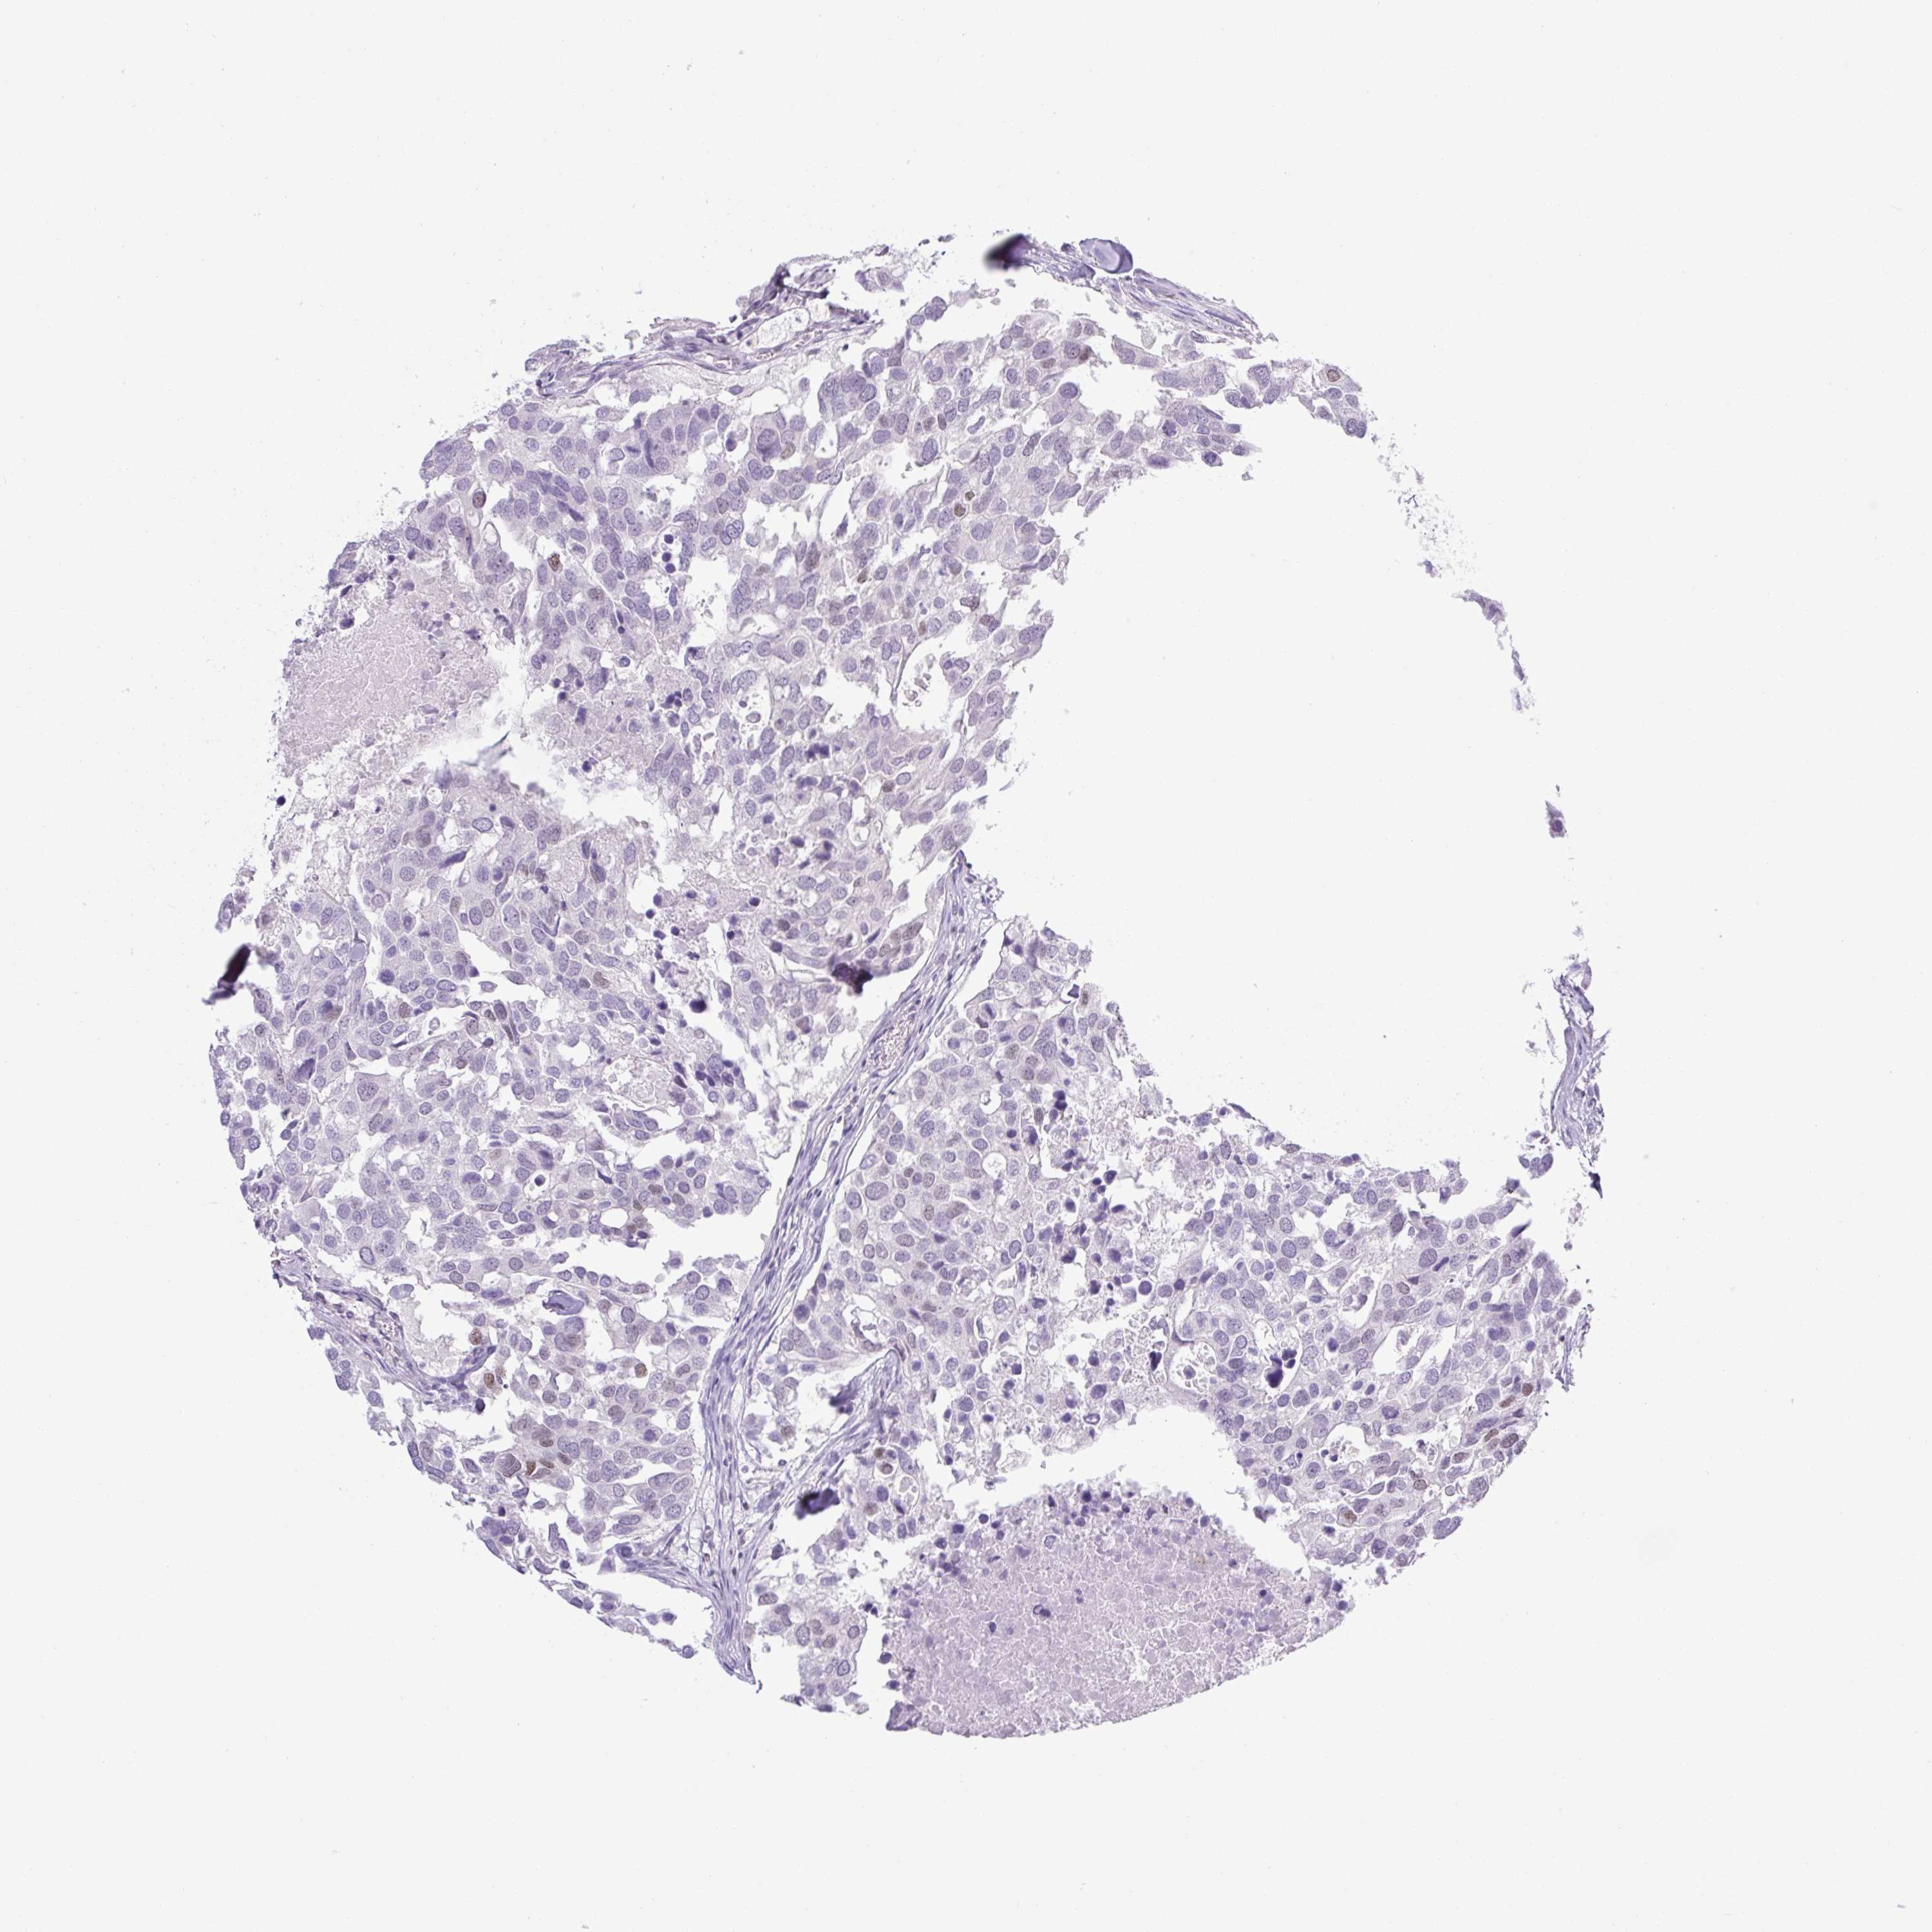

CANCER BREAST CANCER Show tissue menu

BRCA TCGA BRCA VALIDATION PROTEIN EXPRESSION

Breast cancer

Human cancer